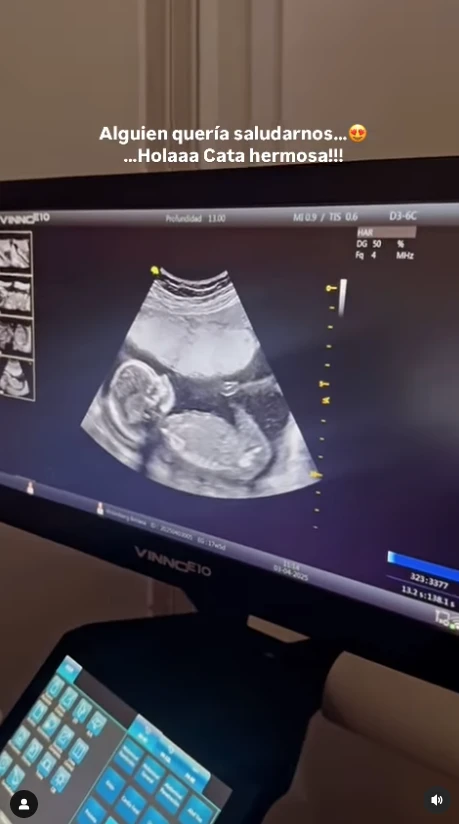

Uno de los momentos más emotivos fue el día de la última transferencia embrionaria. Betiana lo describió como un día “lleno de sensaciones que no se pueden poner en orden: alegría, incertidumbre, agradecimiento, ansiedad, fe”. Y recordó con emoción a Andrea Divita, la médica que los acompañó con sensibilidad durante todo el proceso.

En ese quirófano, la esperanza venció al miedo. “Ese día no solo transferimos una semillita. Ese día le dimos lugar a un sueño que resistió tormentas. Ese día le abrimos el corazón a Catalina”, escribió. En una de las fotos que compartieron, se ve un haz de luz en forma de arcoíris, símbolo del renacimiento tras la tormenta. “Catalina, nuestra beba arcoíris, ya nos estaba enviando un mensaje”, agregó.